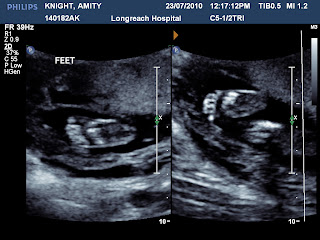

Its feet.